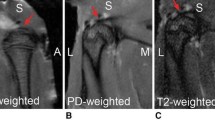

Morikawa et al. described a novel, non-enzymatic, mechanical method for isolating SBDCs for clinical use [45]. According to their technique, subacromial bursa is obtained from over the rotator cuff tendon using an arthroscopic grasper device [45]. The sample is then mechanically digested for 60 s using sterile tenotomy scissors until the tissue resembles a finely minced, liquified particulate (Fig. 4.3) [45].